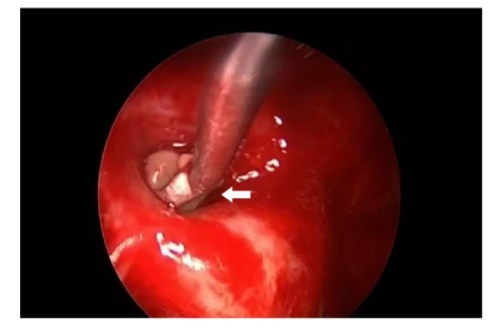

A 64-year-old lady presented to the outpatient department with complaints of headache and right eye blurring of vision for one month. Neurological examination revealed that bitemporal hemianopsia and impairment of visual acuity. Findings from fundus examination were within normal limits. Rest of the brain appeared unremarkable. Endocrine evaluation was normal. Results of renal function tests, liver function tests and haemogram test were within normal limits. A clinical diagnosis of non-secretory pituitary adenoma was made. Magnetic resonance imaging showed a well-circumscribed contrast-enhancing lesion in the sella (Figure 1, Figure 2). The patient underwent an endoscopic endonasal/transsfenoidal surgery in the supine position and total lesion resection was peformed. Intraoperatively, the lesion was found to be yellow colour, soft and avascular and it was removed totally until the sella turcica was visualized (Figure 3).In histopathologic examination septate hyphae were observed between inflammatory cells, Grocott staining is positive, but acid-fast stain for acid-fast bacilli (AFB) was negative. Histopathological findings suggest that infection of Actinomyces (Figure 4, Figure 5). We performed to patient consulted by patients to infectious diseases clinic. Patients underwent intravenous 6x2 gr ampicillin for four weeks.Then oral 4X500 mg amoxicillin treatment is planned a for at least 6 months. Patient did not have any deficits in the next six months.

Figure 3.White arrow shows in intraoperative image that the lesion was found as a yellow colour, soft and avascular shape

White arrow shows in intraoperative image that the lesion was found as a yellow colour, soft and avascular shape